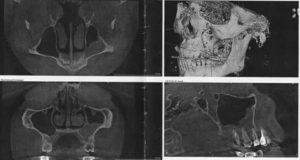

Киста правой верхнечелюстной пазухи носа на снимке

Гиперплазию эпителия можно заметить только на рентгеновских снимках. При подозрении на утолщение врач выдает направление на рентген, который позволит заметить даже минимальное увеличение эпителиального слоя в виде затемнения. Рентген также показывает наличие и уровень жидкости в синусах, а по ее расположению можно определить степень воспаления.

Для дополнительной диагностики используют МРТ и КТ. Применяя метод компьютерной томографии, ЛОР-врач может оценить размеры разрастания, а также проходимость протоков.

Для постановления диагноза используют риноскопию, в ходе которой специалист может обнаружить отечность слизистых оболочек, бледность определенных участков, повреждение сосудов. Если присутствуют симптомы, характерные для хронического гайморита, необходим рентген носовых пазух. Только на рентгеновских снимках можно заметить начальные стадии образований и пристеночный отек.

В больной зоне при пальпации можно обнаружить характерный для кисты «хруст пергамента». На рентгене образование на фоне светлой пазухи выглядит как затемнение кругловатой формы. Подобными клиническими признаками характеризуются кисты как левой, так и правой пазухи.